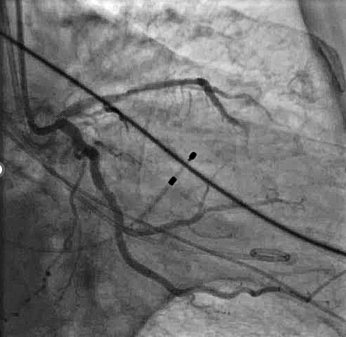

冠脉造影及介入治疗:将ACIST CVi血管造影注射系统调整至冠脉造影模式,完善冠脉造影。结果示:LM未见明显狭窄,LAD近端80%狭窄,严重钙化,IVUS可见360°钙化。回旋支少量斑块浸润,右冠状动脉30-40%狭窄。决定处理LAD,由于患者存在严重钙化,使用Shockwave球囊预处理打开钙化,后植入3.0*24mm +3.5*24mm药物涂层支架,效果满意。